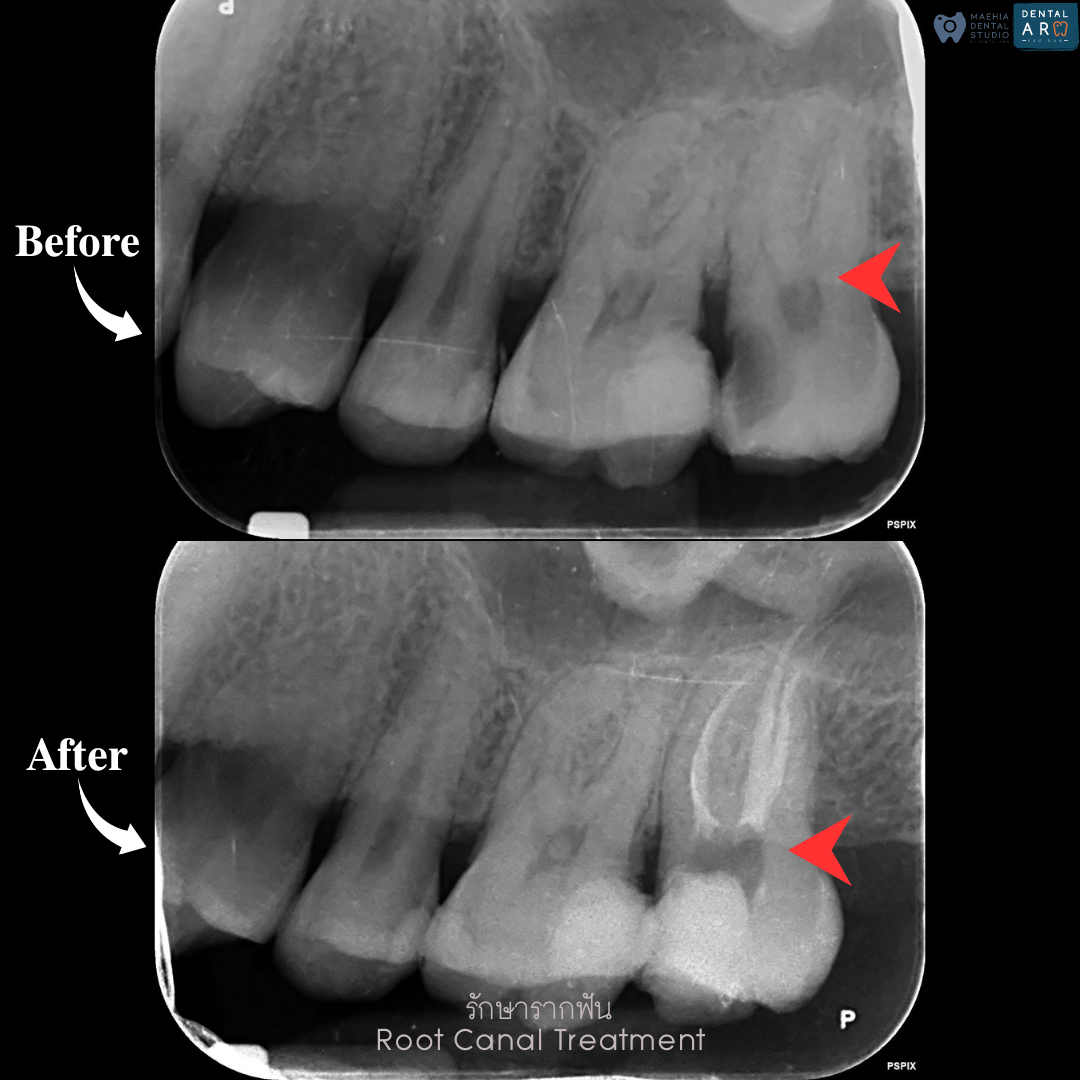

รักษารากฟัน

คือ การรักษาฟันที่เกิดการอักเสบและติดเชื้อภายในโพรงประสาทฟัน และเนื้อเยื่อรอบปลายรากฟัน อันมีสาเหตุมาการอักเสบและติดเชื้อภายในรากฟัน โดยทันตแพทย์จะทำการทำความสะอาดและใส่ยาในคลองรากฟัน และทำการอุดรากฟันเป็นขั้นตอนสุดท้าย การรักษารากฟันจะช่วยเก็บรักษาฟันให้สามารถคงอยู่ในช่องปากต่อได้ โดยไม่ต้องถอนฟันและไม่ต้องใส่ฟันทดแทน